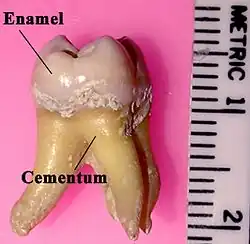

Im Oberkiefer haben die menschlichen Molaren drei oder mehr Wurzeln. Eine sehr kräftige auf der Gaumenseite (palatinale Wurzel) und zwei kleinere auf der Wangenseite (vestibulär). Von diesen wiederum ist eine Wurzel vorne (mesial) und die andere hinten (distal). Die beiden vestibulären Wurzeln werden korrekt als mesio-vestibuläre Wurzel und als disto-vestibuläre Wurzel bezeichnet. Im Praxisalltag wird aber einfach nur kurz von der distalen, mesialen und palatinalen Wurzel gesprochen. Pro Wurzel findet sich mindestens ein Wurzelkanal. Mesio-vestibuläre Wurzeln haben mitunter zwei Kanäle.

Im Unterkiefer haben die Molaren zwei Wurzeln. Davon liegt eine Wurzel mesial (vorne) und eine Wurzel distal (hinten). Pro Wurzel findet sich mindestens ein Wurzelkanal. Die mesiale Wurzel hat jedoch in der Mehrzahl der Fälle zwei Kanäle – ein Kanal liegt vestibulär (auf der Wangenseite) und der andere lingual (auf der Zungenseite).